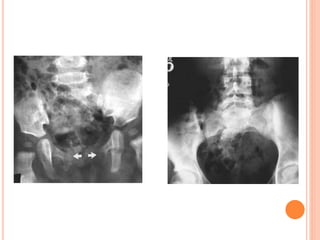

KUB ANALYSIS

 Musculoskeletal: evaluate all bone elements.

 Psoas muscle margin: straight, convex or absent.

 Intestinal gas: overlap, displaced.

 Kidneys

 Calcifications: overlying the UT or outside.

 Gas shadow: abnormal air at UT.